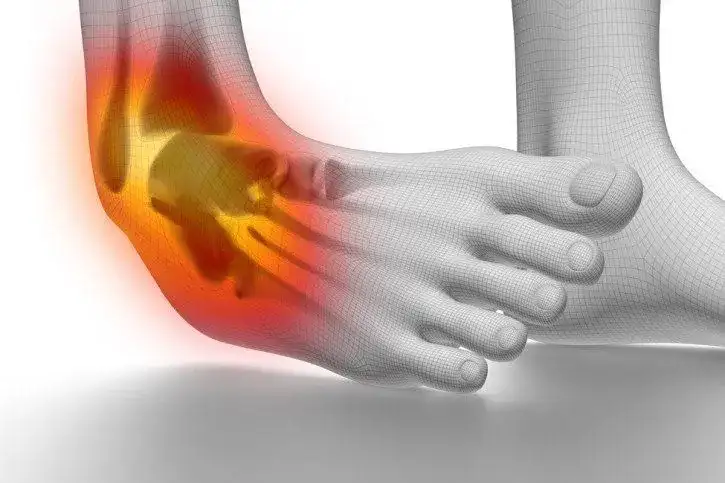

Ile czasu goi się skręcenie stawu skokowego? Poznaj kluczowe informacje

Ile czasu goi się skręcenie stawu skokowego? Dowiedz się, jakie czynniki wpływają na czas regeneracji i jak skutecznie przyspieszyć powrót do zdrowia.